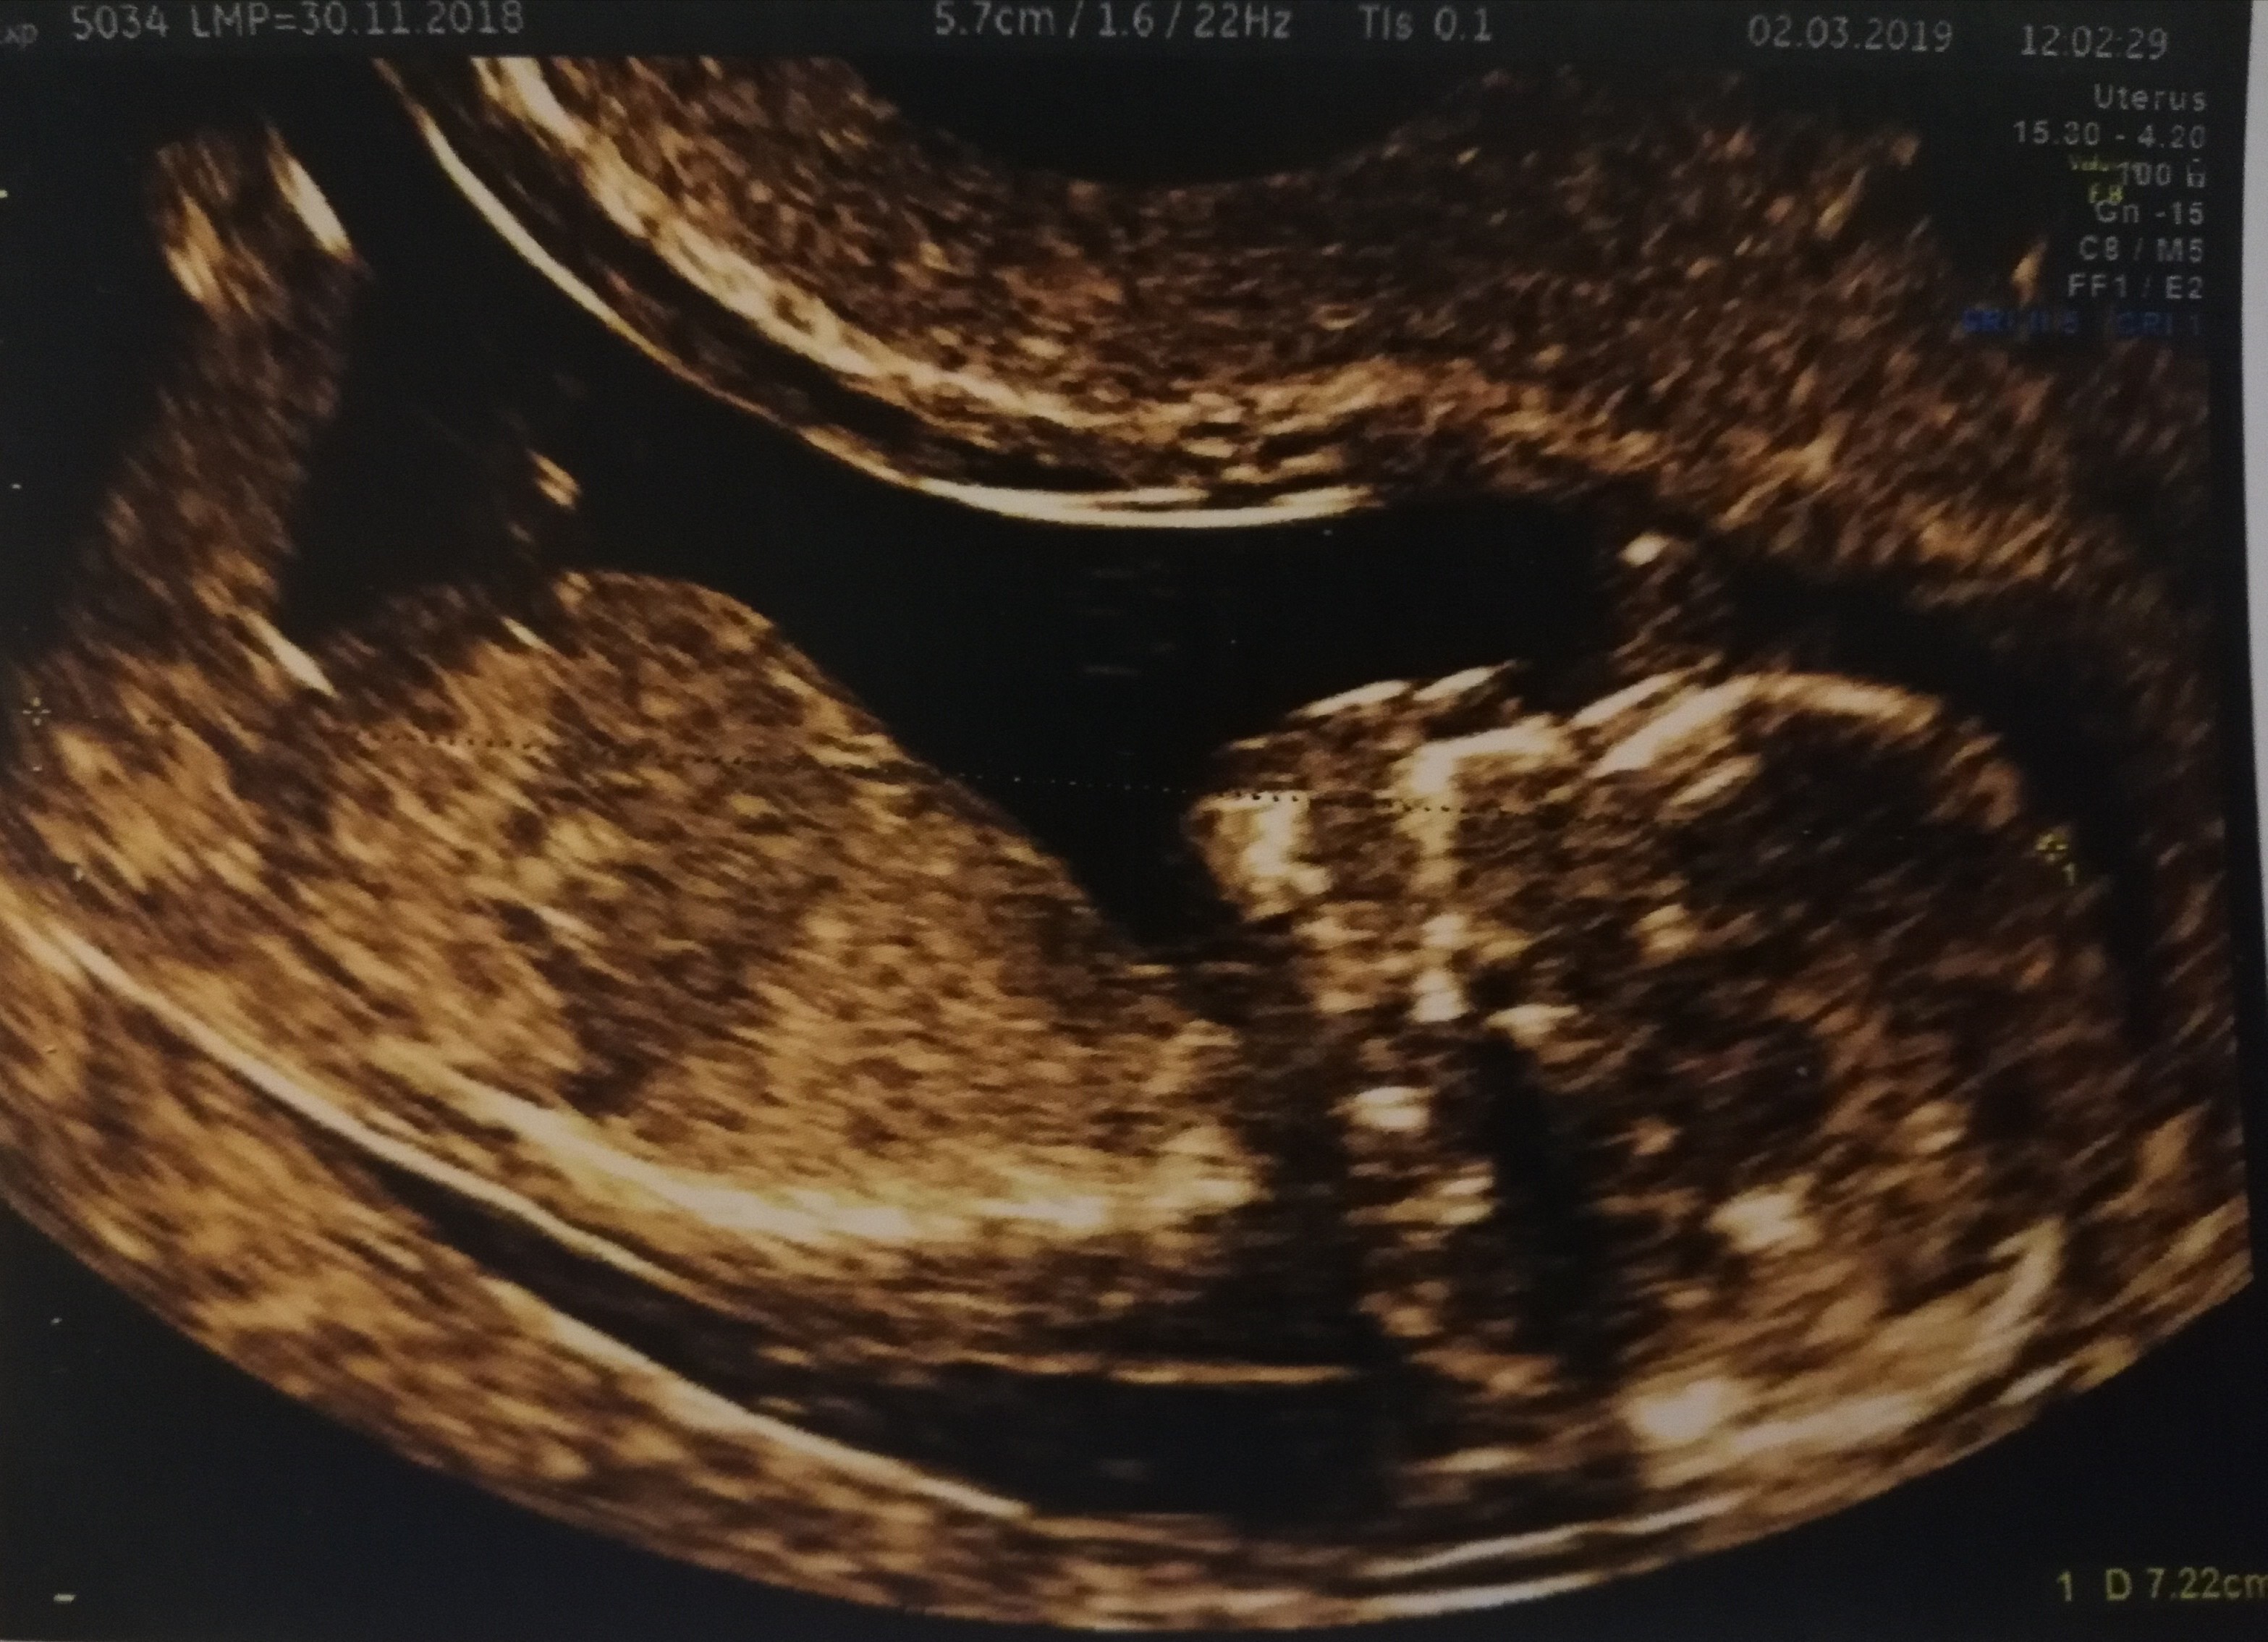

Ginekolog na prenatalnych nie powiedział mi nic co do płci.

Ale dziś tak przeglądam neta i mamaginekolog pisze właśnie o wyrostku na tym najprostszym zdj maluszka, czy uniesiony do góry czy do dołu(drugie zdjęcie) powiedzcie mi, czy po naszym można coś jednak podejrzewać, przypuszczać? :p :p

Załączniki

• IMG_20190302_182158.jpg

IMG_20190302_182158.jpg

1,1 MB · Wyświetleń: 651